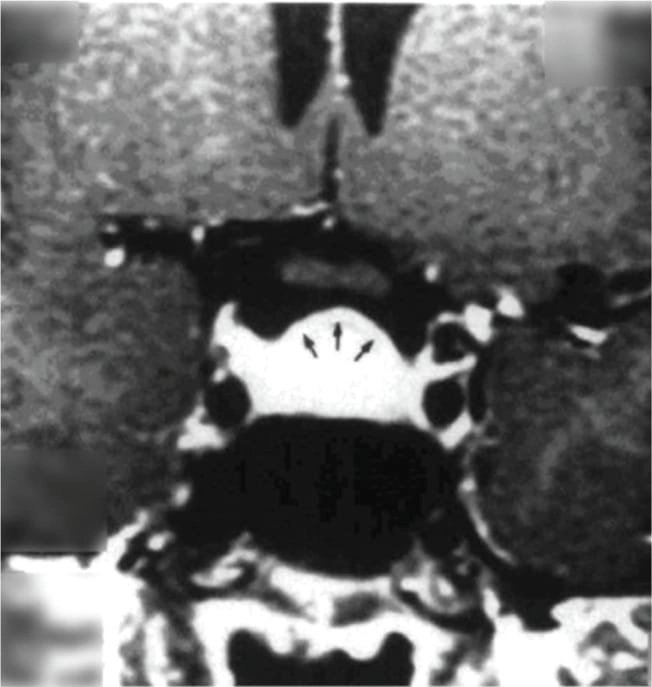

তবে পিটুইটারি হাইপারপ্লাসিয়া দেখা যায় প্রাইমারি গনাডাল, অ্যাডরিনাল বা হাইপোথাইরয়েডিজমের মত এন্ড অর্গান ইনসাফিসিয়েন্সিতে। বিশেষ করে, অব্যবহৃত প্রাইমারি হাইপোথাইরয়েডিজমে পিটুইটারি হাইপারপ্লাসিয়া পূর্বের ধারণার তুলনায় অনেক বেশি দেখা যায়। ২০১৯ সাল পর্যন্ত এরকম ১০৫টি কেস রিপোর্ট করা হয়েছে। এই ধরনের হাইপারপ্লাসিয়া গম্বুজ-আকৃতির (dome-shaped) হয়ে অপটিক কায়াজমাকে চেপে ধরতে পারে, যার ফলে অপারেশনের প্রয়োজন পড়তে পারে—যেমনটা আমাদের তৃতীয় কেসে ঘটেছিল।

কেস ২: একই রকমভাবে, ১৫ বছর বয়সী আরও একজন কিশোরী অল্প উচ্চতা ও টিউমার সন্দেহে নিউরোসার্জেনের কাছে রেফার করা হয়। তার TSH ছিল 100 এবং MRI-তে একটি ডোম-আকৃতির টিউমার দেখা যায়। যাকে ওষুধের চিকিৎসায় সত্য জীবনে ফিরিয়ে আনা হয় এবং ৬ মাসে তার উচ্চতা বৃদ্ধি পায় ও নিয়মিত মাসিক শুরু হয়। MRI-তে টিউমার সম্পূর্ণ অদৃশ্য হয়ে যায়।

চিকিৎসক তথা আবিষ্কারক সত্যম তিনটি কেসের বিষয় নিয়ে যখন তুলনা করতে নিলেন এবং পুরনো সৃষ্টি ঘাটতে শুরু করলেন তখন তিনি দেখতে পান সবগুলি ক্ষেত্রেই একই রকম সাদৃশ্য অর্থাৎ পিটুইটারি গ্রন্থি মাঝের অংশ এই গ্রন্থি দেখতে খানিকটা প্রজাপতির মতোই এবং তার মাঝের অংশের (প্রজাপতির দেহের উপরের অংশ মাথার মতই দেখতে) উপরের ভাগ সব ক্ষেত্রেই ডোমের মত বা গম্বুজ আকৃতির। তিনি এই ডোম বা গম্বুজ আকৃতি হওয়ার কারণ বিশ্লেষণ করতে গিয়ে দেখেন পিটুইটারির সামনের অংশ যেখানে থাইরোট্রপগুলো থাকে, যেখান থেকে এই টিউমারটি হয়। আর যখনই এটি বাড়বে তখন টমের মতনই তৈরি হবে। অর্থাৎ গম্বুজ আকৃতির। আর সেখান থেকেই ডোম-সাইনের উৎস অর্থাৎ আবিষ্কার।

MRI-তে এই হাইপারপ্লাসিয়া সাধারণত গম্বুজ-আকৃতির ও সমমিত হয় এবং হোমোজেনাস সিগনাল ইন্টেনসিটি দেখায়, যেখানে সাধারণ নন-ফাংশনাল পিটুইটারি অ্যাডেনোমা নানা আকার ও অসমতা নিয়ে দেখা যায়।

পূর্ববর্তী গবেষণাগুলিও এই ‘Dome Sign’-এর গুরুত্ব তুলে ধরেছেন, যেমন ডঃ আহমেদ (১৯৮৯), ডঃ সারলিস (২০০০), ডঃ ফ্রান্সেস্কি ও পাসেরি (২০১১) এবং ডঃ শুক্লা (২০১৯)। এসব গবেষণায় MRI-তে ডোম-আকৃতির হাইপারপ্লাসিয়া শণাক্ত হয়েছে যা লেভোথাইরক্সিন চিকিৎসার মাধ্যমে কয়েক সপ্তাহের মধ্যেই হ্রাস পেয়েছে।

তাঁর দাবি, MRI-তে ‘DOME Sign’ থাকা এবং TSH বাড়তি থাকলে, সেটি হাইপোথাইরয়েডিজম-জনিত হাইপারপ্লাসিয়ার সম্ভাবনার কথা নির্দেশ করে এবং এই রোগীদের শুধুমাত্র লেভোথাইরক্সিন দিয়ে চিকিৎসা করলে পূর্ণ আরোগ্য সম্ভব।